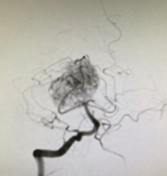

血管造影:椎骨動脈撮影では右後大脳動脈から多数の栄養血管を認め、腫瘍が濃く染まっています。

後大脳動脈のとても小さな栄養血管からNBCAを注入していきます。

約半分の栄養血管が閉塞してきました。

終盤は外頚動脈の中硬膜動脈からNBCAを注入しながら塞栓を続けます。

最終的に血管描出像は消失しました。